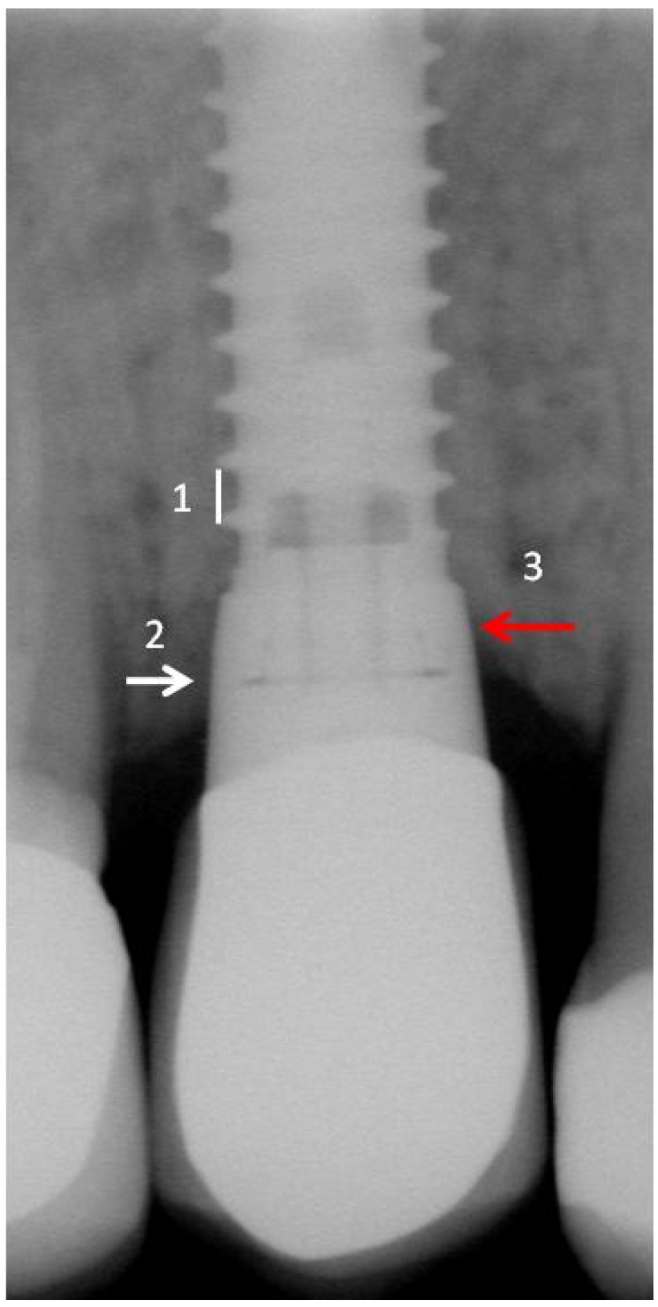

4.4. Periodontal and Radiologic Parameters